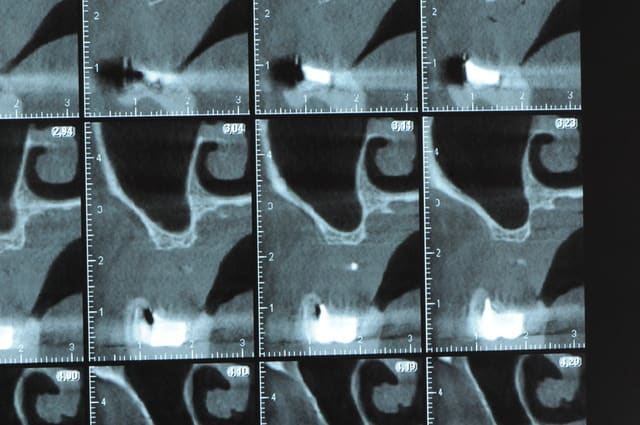

Une petite étude de ton cas D57

Les zones exploitables radiologiquement parlant:

Coupes implant

2,3 40100

4,96 35130 avec sinus lift mais difficile

5,25 35150

6,02 35130

6,78 35115 après réduction de hauteur de crête

7,26 35115 après réduction de hauteur de crête

8,51 35150

10,43 40115 ou 50115

11,10 40115

Ce qui nous fait 9 implants possible évidement avec un comblement de sinus on augmenterait encore les zones implantable mais ce n’est pas le but recherché, avec 8 (4+4) il doit être possible de faire une belle barre support de complet